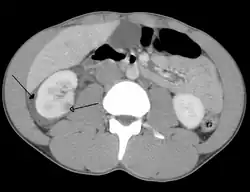

A large hematoma (closed arrow) of the left kidney (open arrow)

The kidneys may also be injured; they are somewhat but not completely protected by the ribs.[6] Kidney lacerations and contusions may also occur.[13] Kidney injury, a common finding in children with blunt abdominal trauma, may be associated with bloody urine.[13] Kidney lacerations may be associated with urinoma or leakage of urine into the abdomen.[4] A shattered kidney is one with multiple lacerations and an associated fragmentation of the kidney tissue.[4]